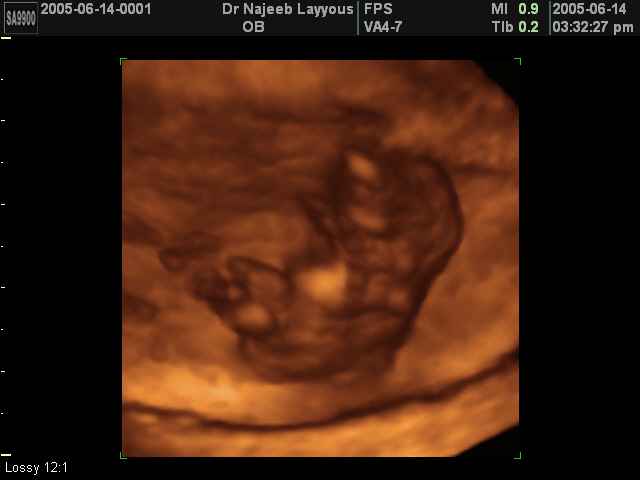

3D First Trimester Ultrasound Scan Photos